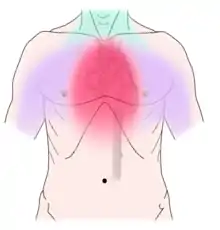

Non-dental causes of toothache are much less common as compared with dental causes. In a toothache of neurovascular origin, pain is reported in the teeth in conjunction with a migraine. Local and distant structures (such as ear, brain, carotid artery, or heart) can also refer pain to the teeth.[35]: 80, 81 Other non-dental causes of toothache include myofascial pain (muscle pain) and angina pectoris (which classically refers pain to the lower jaw). Very rarely, toothache can be psychogenic in origin.[10]: 57–58

Non-dental sources of pain often cause multiple teeth to hurt and have an epicenter that is either above or below the jaws. For instance, cardiac pain (which can make the bottom teeth hurt) usually radiates up from the chest and neck, and sinusitis (which can make the back top teeth hurt) is worsened by bending over.[10]: 56, 61 As all of these conditions may mimic toothache, it is possible that dental treatment, such as fillings, root canal treatment, or tooth extraction may be carried out unnecessarily by dentists in an attempt to relieve the individual's pain, and as a result the correct diagnosis is delayed. A hallmark is that there is no obvious dental cause, and signs and symptoms elsewhere in the body may be present. As migraines are typically present for many years, the diagnosis is easier to make. Often the character of the pain is the differentiator between dental and non-dental pain.

Establishing a diagnosis of nondental toothache is initially done by careful questioning about the site, nature, aggravating and relieving factors, and referral of the pain, then ruling out any dental causes. There are no specific treatments for nondental pain (each treatment is directed at the cause of the pain, rather than the toothache itself), but a dentist can assist in offering potential sources of the pain and direct the patient to appropriate care. The most critical nondental source is the radiation of angina pectoris into the lower teeth and the potential need for urgent cardiac care.[10]: 68